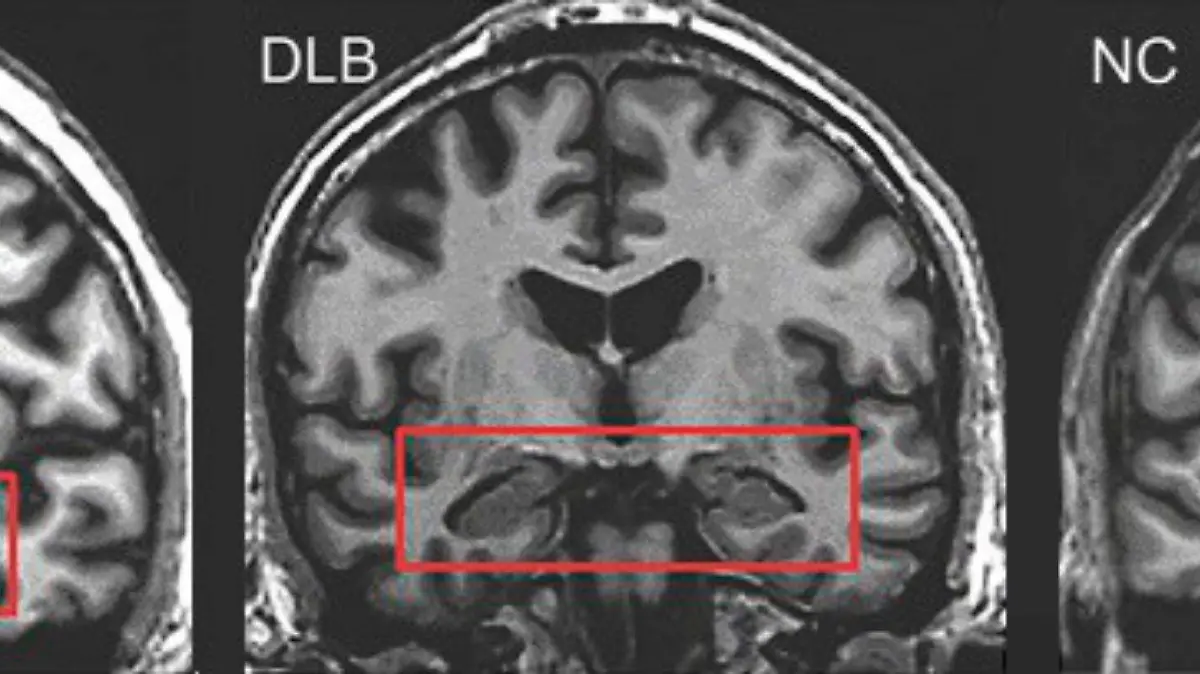

Dejar el alcohol después de los 65: lo que la ciencia revela sobre el cerebro y la memoria

El consumo de alcohol en adultos mayores puede acelerar problemas de memoria y aumentar el riesgo de Alzheimer. Descubre cuáles hábitos pueden proteger tu mente.

El envejecimiento cerebral no perdona